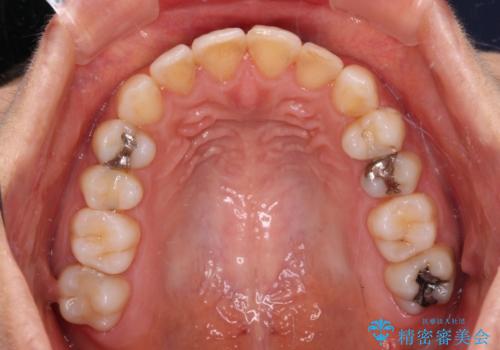

前歯の叢生をいつの間にか改善 インビザラインによる矯正治療

- 前歯のデコボコを気にして来院された患者様です。

IPR(歯と歯の間を削る)によってデコボコが解消するように設計し、インビザラインにより治療を行うこととしました。

下顎善の叢生をもう少し改善したかったのですが、患者様は十分に整ったとのことで治療を終えることになりました。